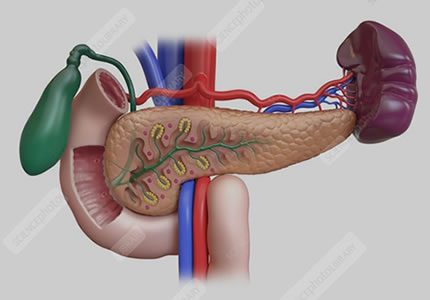

Pancreas & Spleen

- This combined assessment evaluates the pancreas for cysts, inflammation (pancreatitis), ductal dilation, or structural changes that may suggest a digestive obstruction. We also measure the spleen to check for enlargement (splenomegaly), internal texture changes, or signs of past infection. This survey is particularly useful for identifying the cause of persistent pain in the upper-left or central abdomen.

- £150

- Ideal for: Deep-seated abdominal pain, suspected pancreatitis, left-sided discomfort, and comprehensive digestive health reviews.

- This targeted scan assesses the pancreas for cysts, inflammation (pancreatitis), or ductal dilation that may suggest a digestive obstruction or malignancy. By using high-resolution imaging, we can identify subtle structural changes, mass lesions, or calcifications that are often the cause of deep-seated, persistent pain in the upper-central abdomen.

- £150

- Ideal for: Investigating deep abdominal or mid-back pain, suspected pancreatitis, unexplained weight loss, or follow-up of known pancreatic cysts

- Detects splenomegaly, infarcts, trauma, cysts, and accessory spleens. Indicated in haematological conditions or systemic infections.

- £150